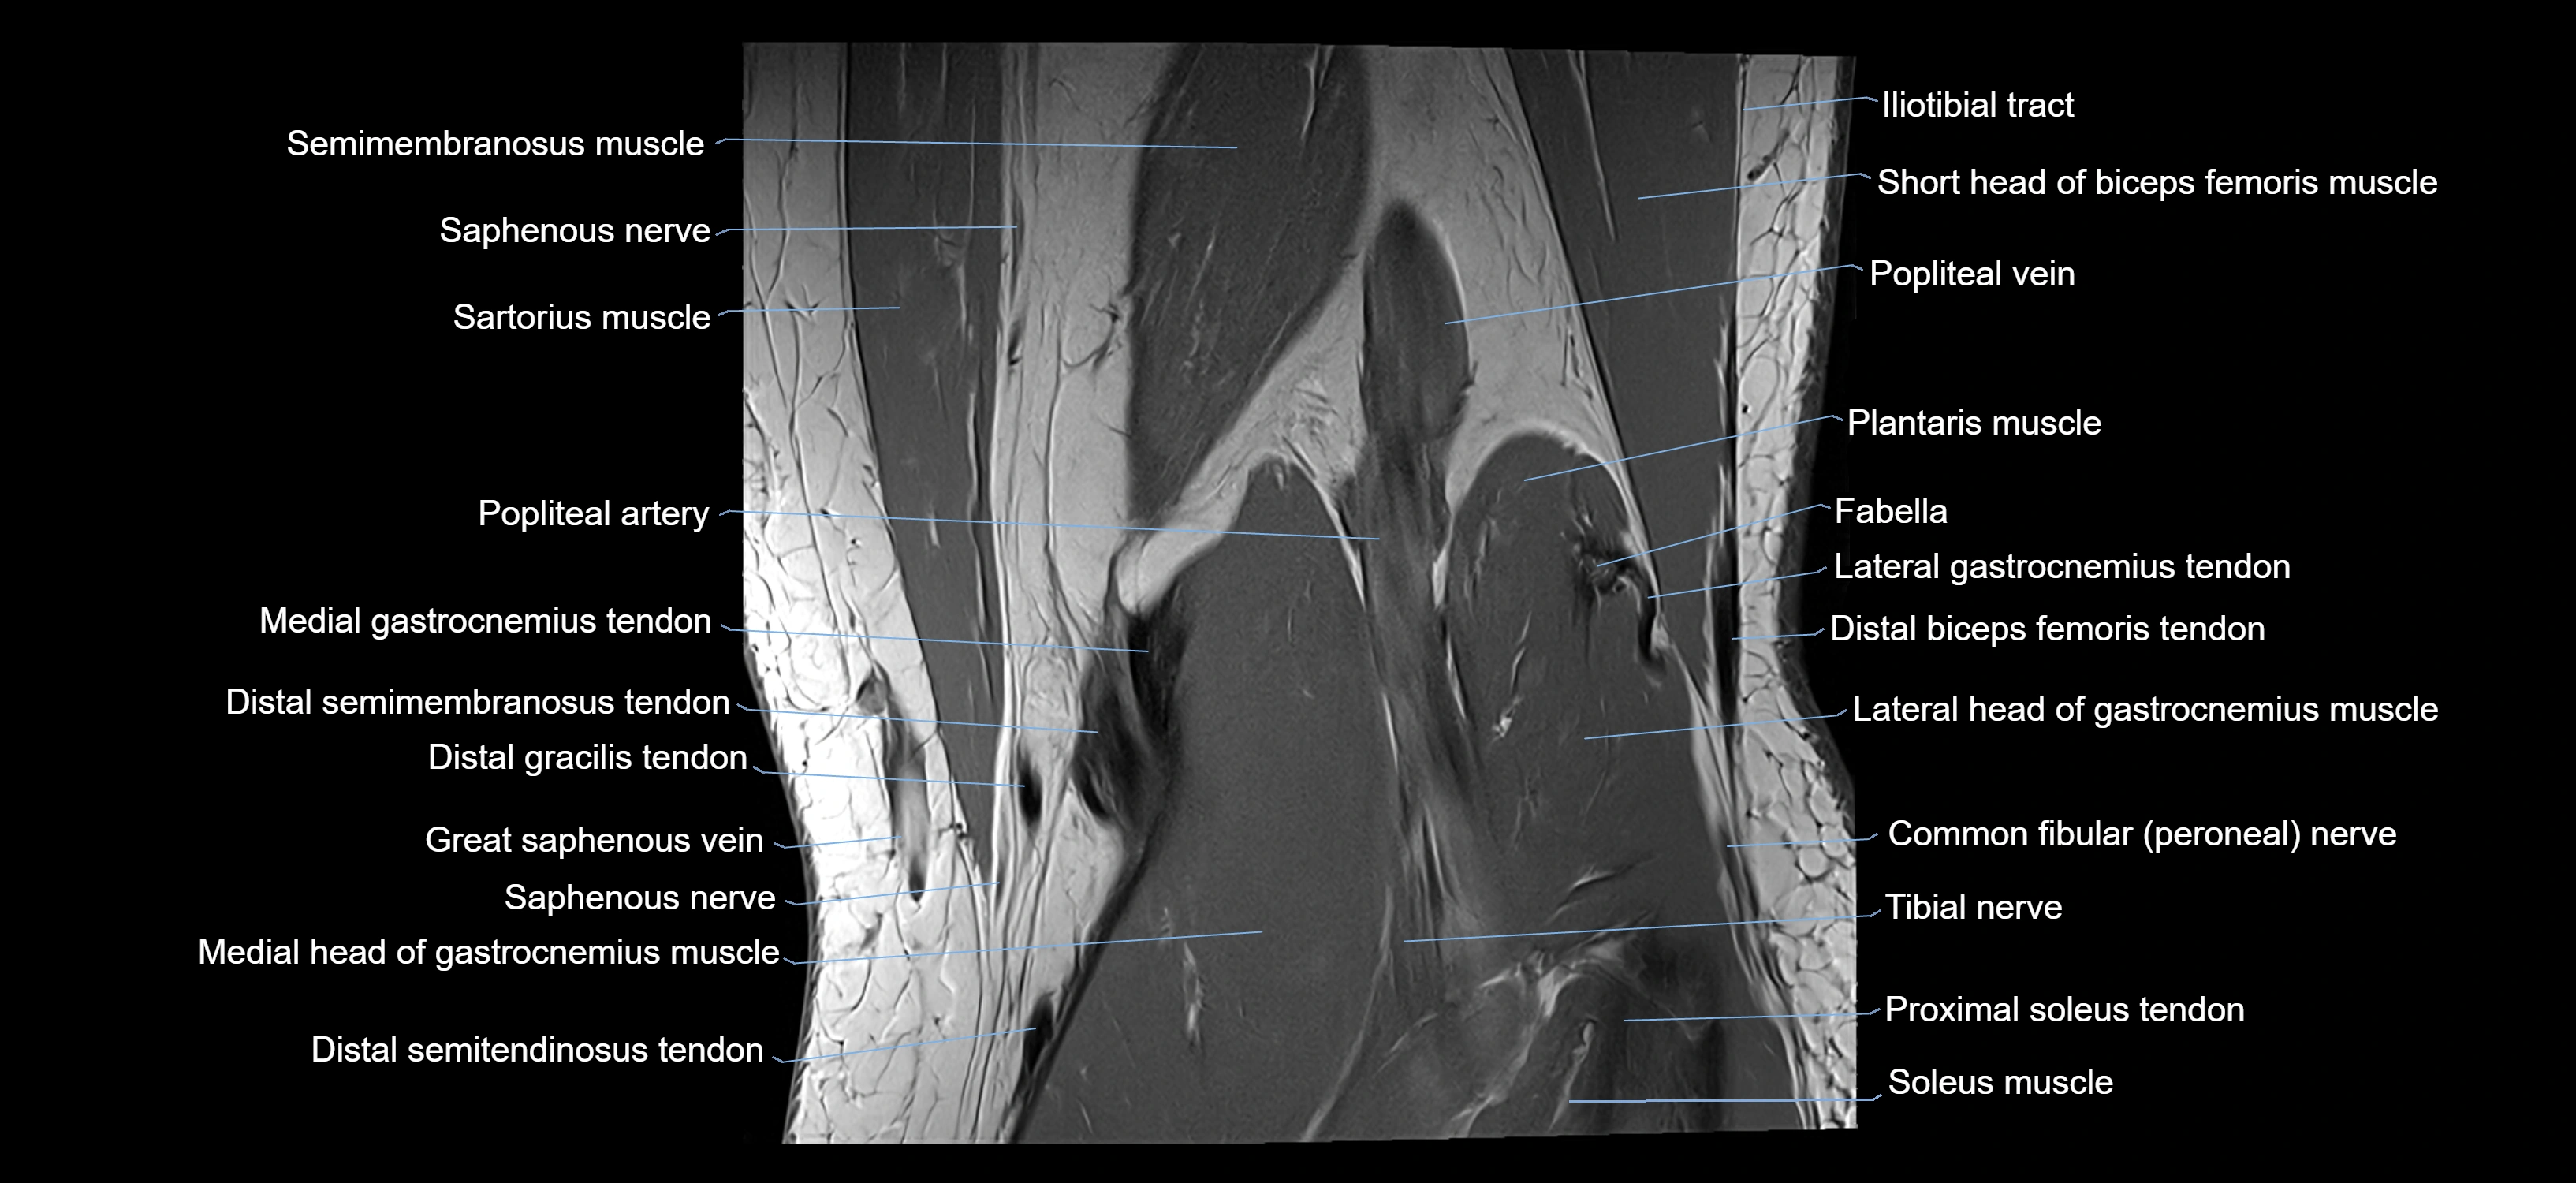

- Popliteal artery

- Popliteal vein

- Saphenous nerve

- Sartorius muscle

- Semimembranosus muscle

- Medial gastrocnemius tendon

- Medial head of gastrocnemius muscle

- Soleus muscle

- Tibial nerve

- Lateral gastrocnemius tendon

- Lateral head of gastrocnemius muscle

- Plantaris muscle